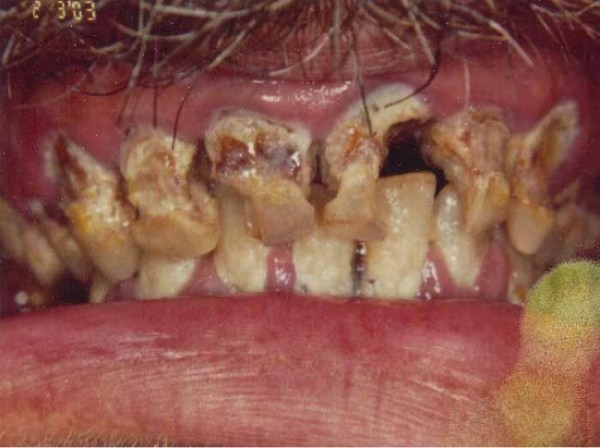

Methamphetamine makes people high, but chronic meth use also heightens the risk for dental destruction.